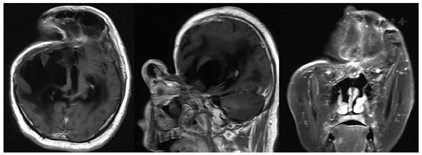

术前增强MRI,术前CT检查齐全,颅骨三维重建。

入院后,考虑其颅骨缺损处皮肤凹陷严重,科室讨论后决定先予以分流管夹闭(分流泵调压失败),使脑室暂时性扩张,恢复头部外形并改善皮肤张力,同时加用甘露醇+激素予以脑功能保护(图1)。引流管夹闭5 d后,患者意识基本与夹闭前相似,脑室明显扩张,伴室旁水肿,颞顶部皮肤较前膨隆,但前额部皮肤由于窦道与前颅底炎性粘连,凹陷严重,缓解不佳(图2、图3)。